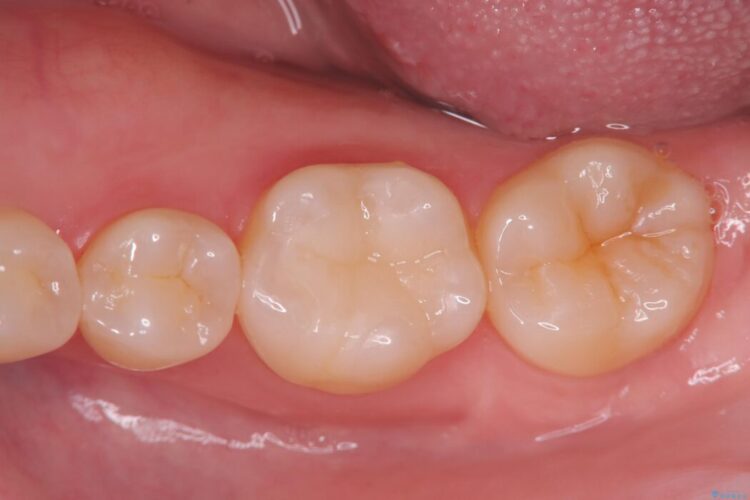

欠けた奥歯をPGAで補強。違和感のない咬み心地へ

欠けた奥歯をPGAで補強。違和感のない咬み心地へ ビフォー 欠けた奥歯をPGAで補強。違和感のない咬み心地へ アフター

以前治療した奥歯(右下7番)の詰め物が欠けてしまったとご来院された患者様です。